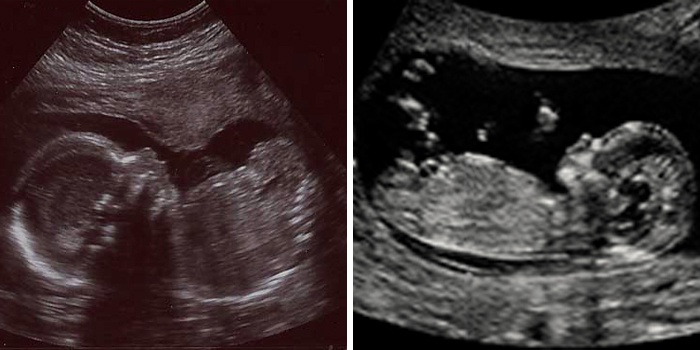

Беременность 22 недели мальчик

Беременность 22 недели мальчик 115 фото